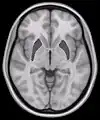

![]() Coronal section of brain through intermediate mass of third ventricle. (Putamen labeled at top.) | |

Horizontal slice of MRI-image showing the putamen. The other nuclei of the basal ganglia (caudate nucleus and globus pallidus) can be seen as well.